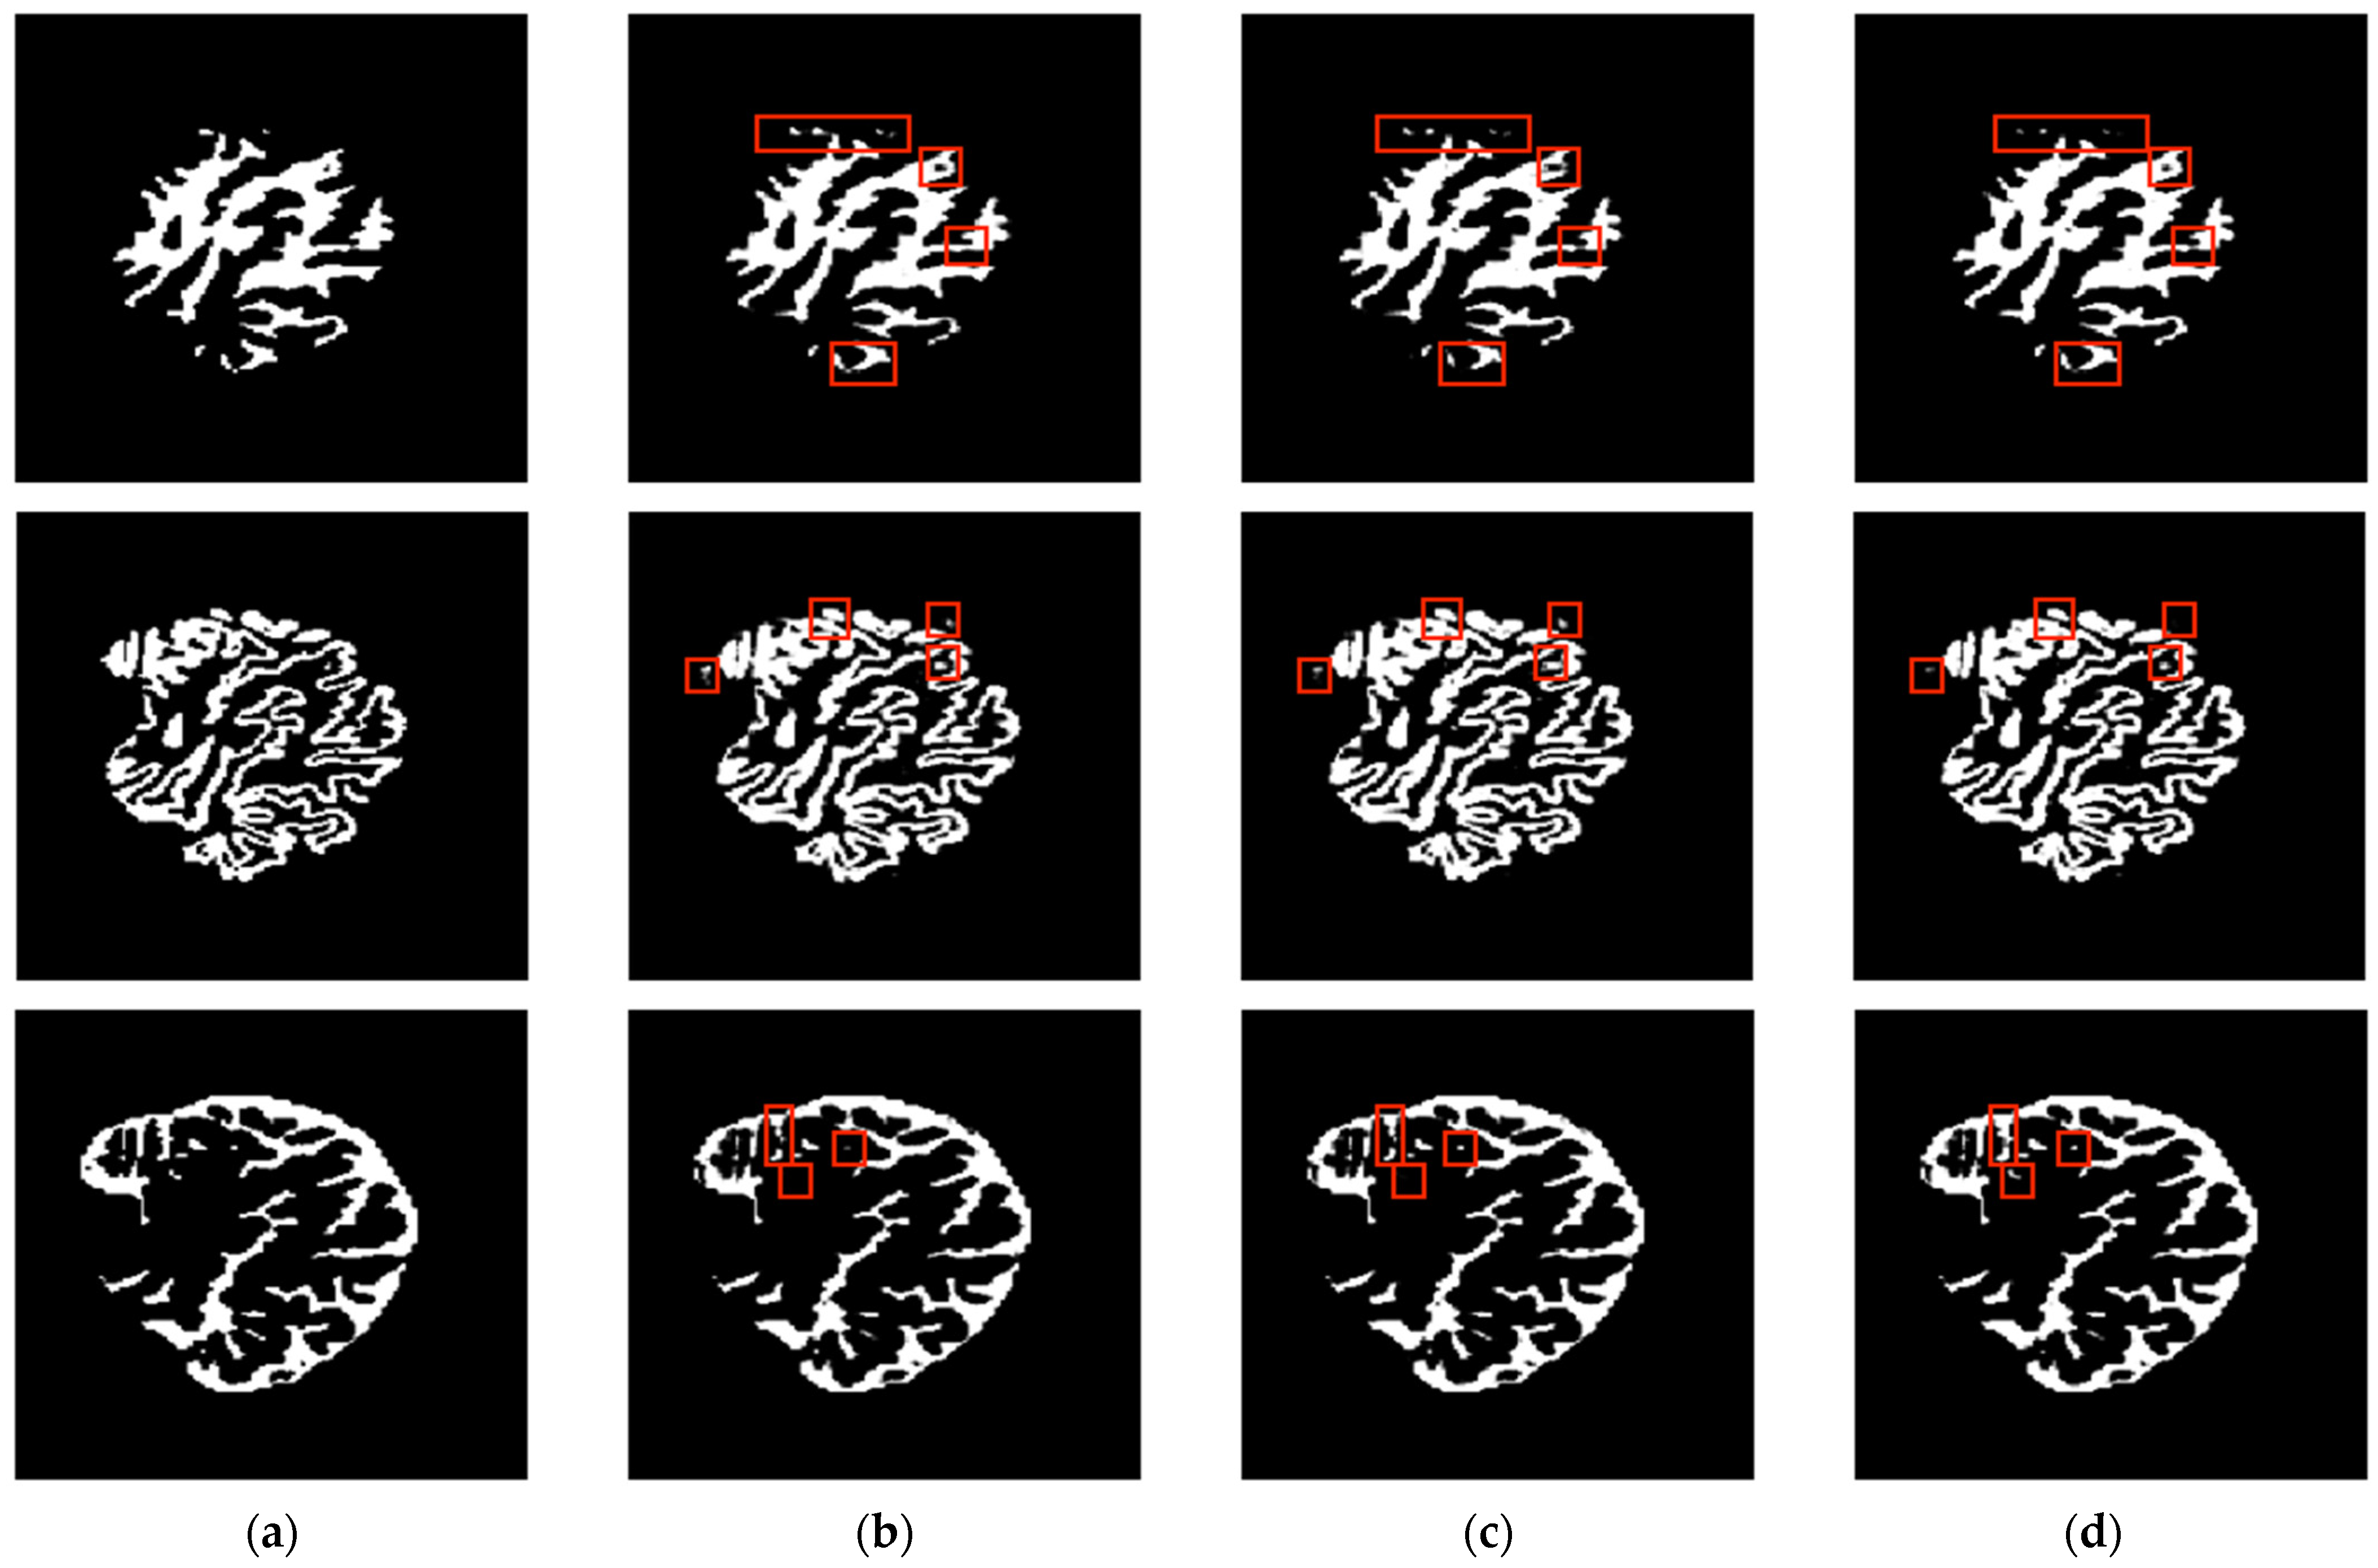

3.1. Analysis and Comparison with Single-Slice and Multiple-Slice Input UNet

3.2. Comparisons with Other Methods